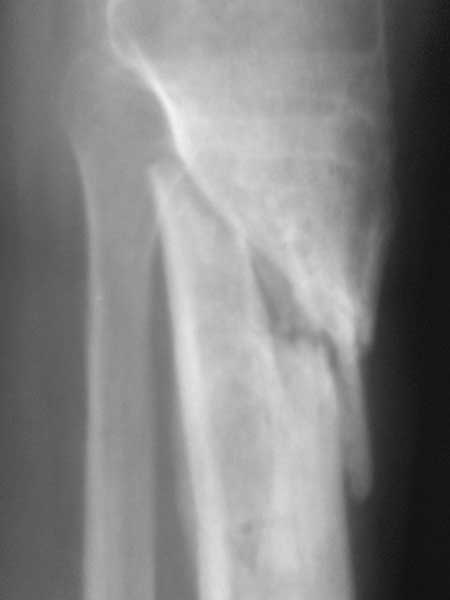

Спасибо за обсуждение.Отправил остальные R, изиняюсь за качество.

2.Возникновение раны склонен связывать с эпизодом спицевой инфекции нашедшей себе "уютное место" в плохо васкулизированных интерпонироанных мягких тканях между отломками. Я думаю что нет разницы где ложный сустав( в губчатой или др.) -он будет если там интерпозиция.

3.Перелом на 2 уровнях, есть искривление костно-мозгового канала. Проксимальный отломок короткий.